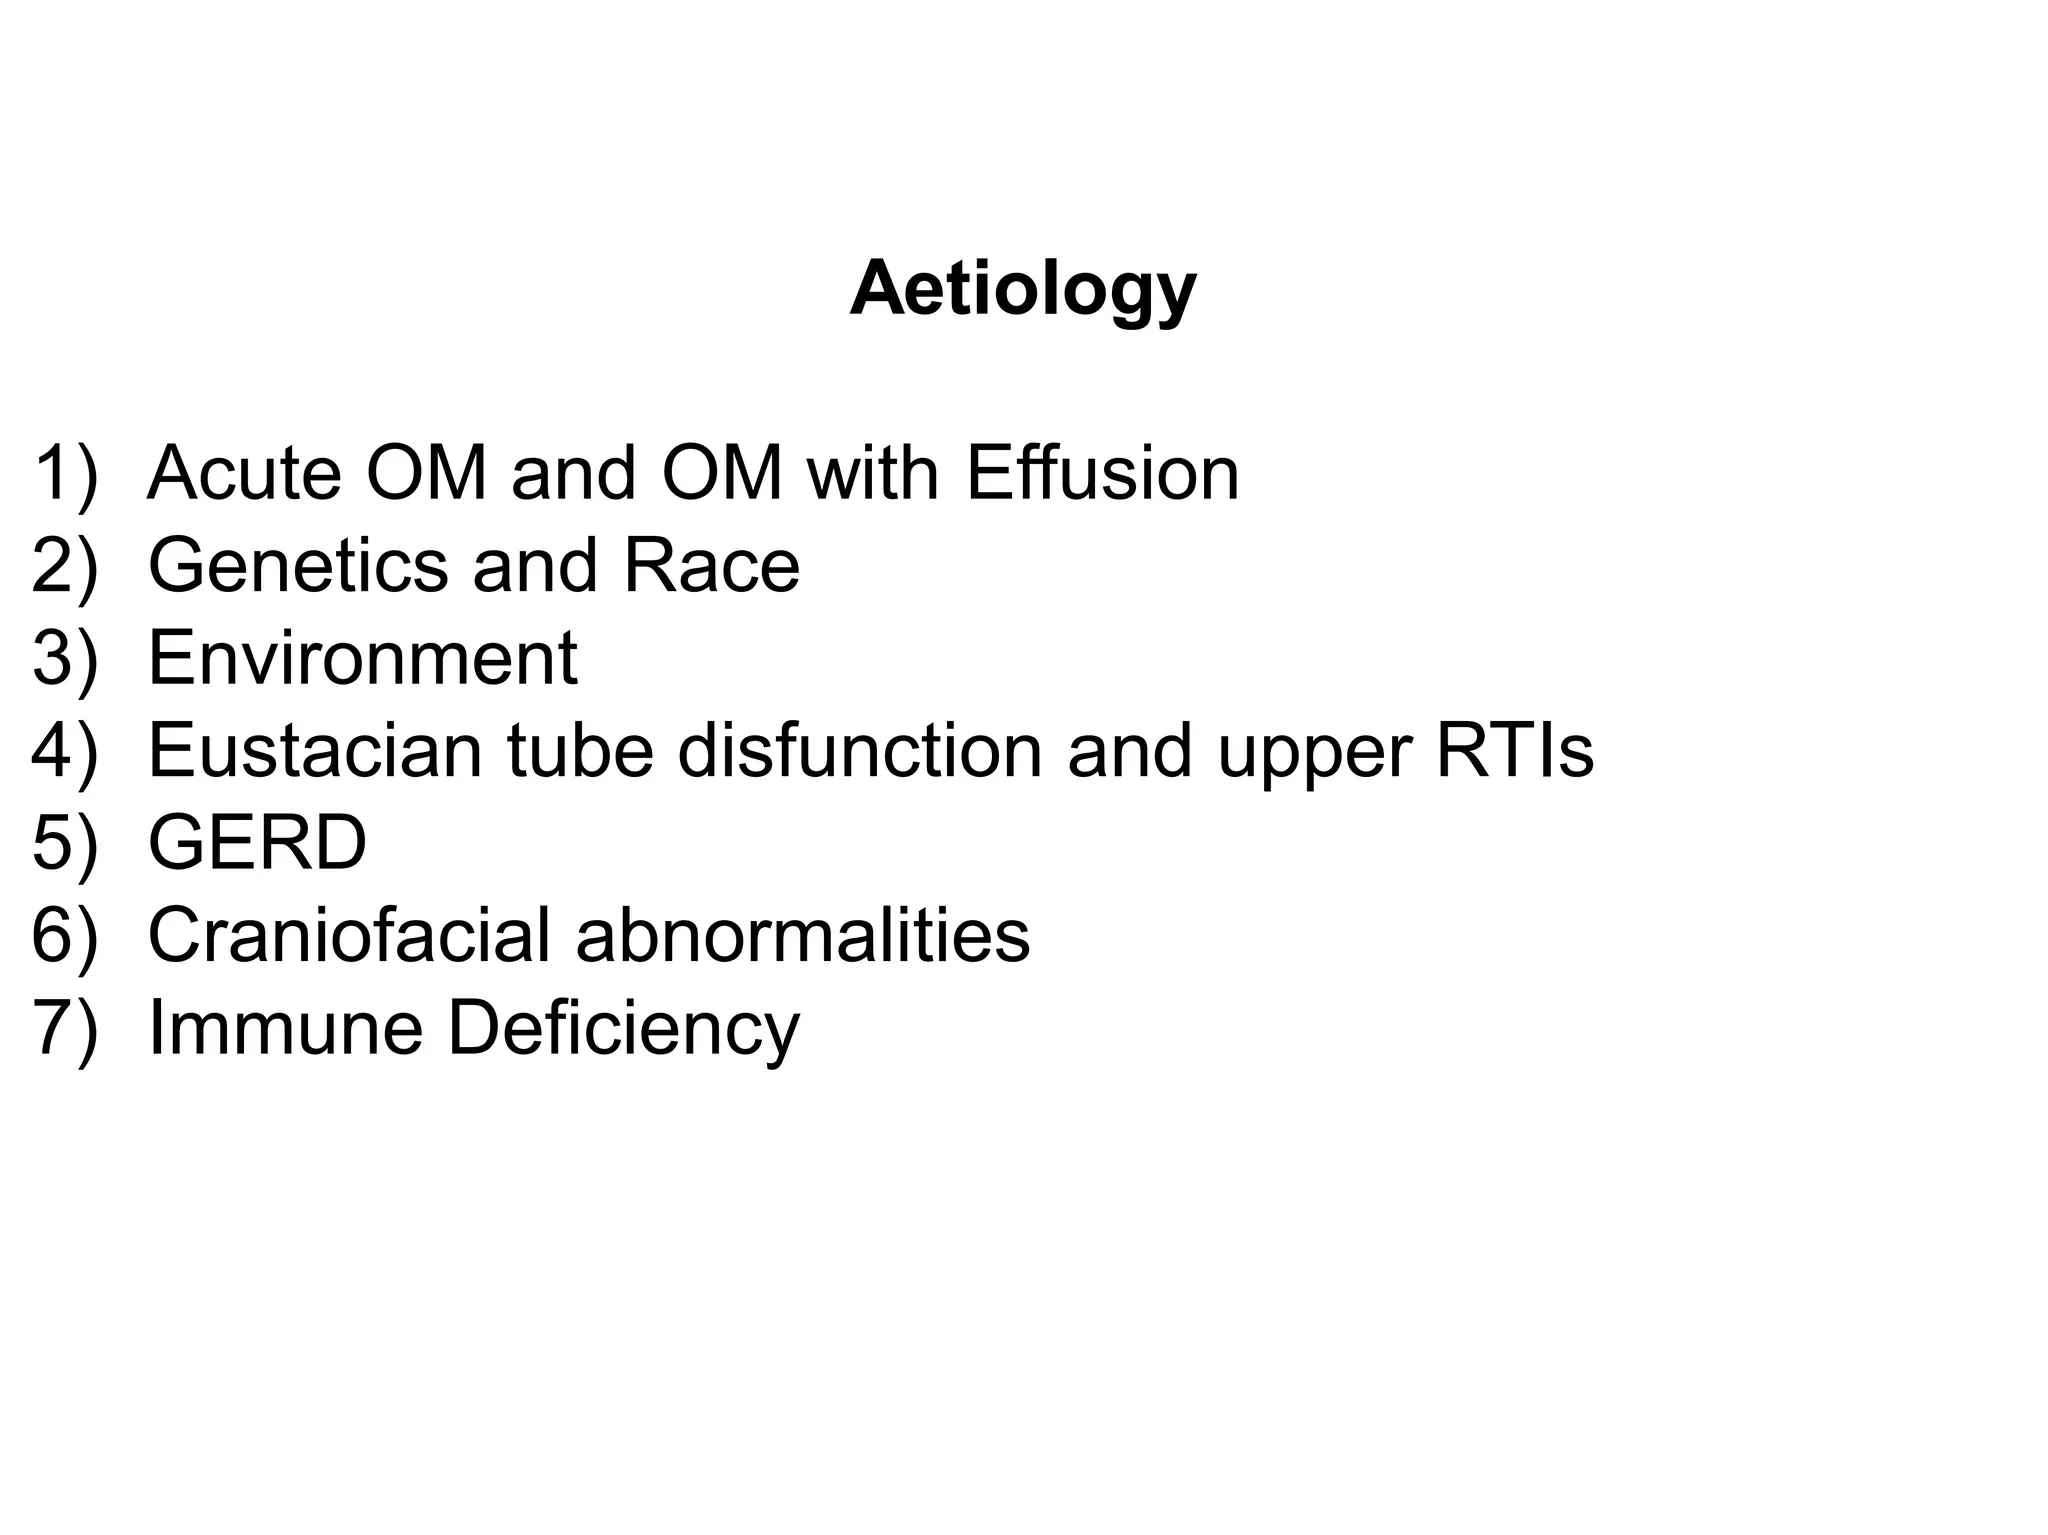

Chronic otitis media is a chronic inflammation of the middle ear and mastoid cavity that presents with recurrent ear discharge through a perforated eardrum. It has several subtypes depending on the state of the eardrum perforation and epithelium. It can be caused by prior acute otitis media, genetics, environment, eustachian tube issues, gastroesophageal reflux disease, craniofacial abnormalities, or immune deficiency.